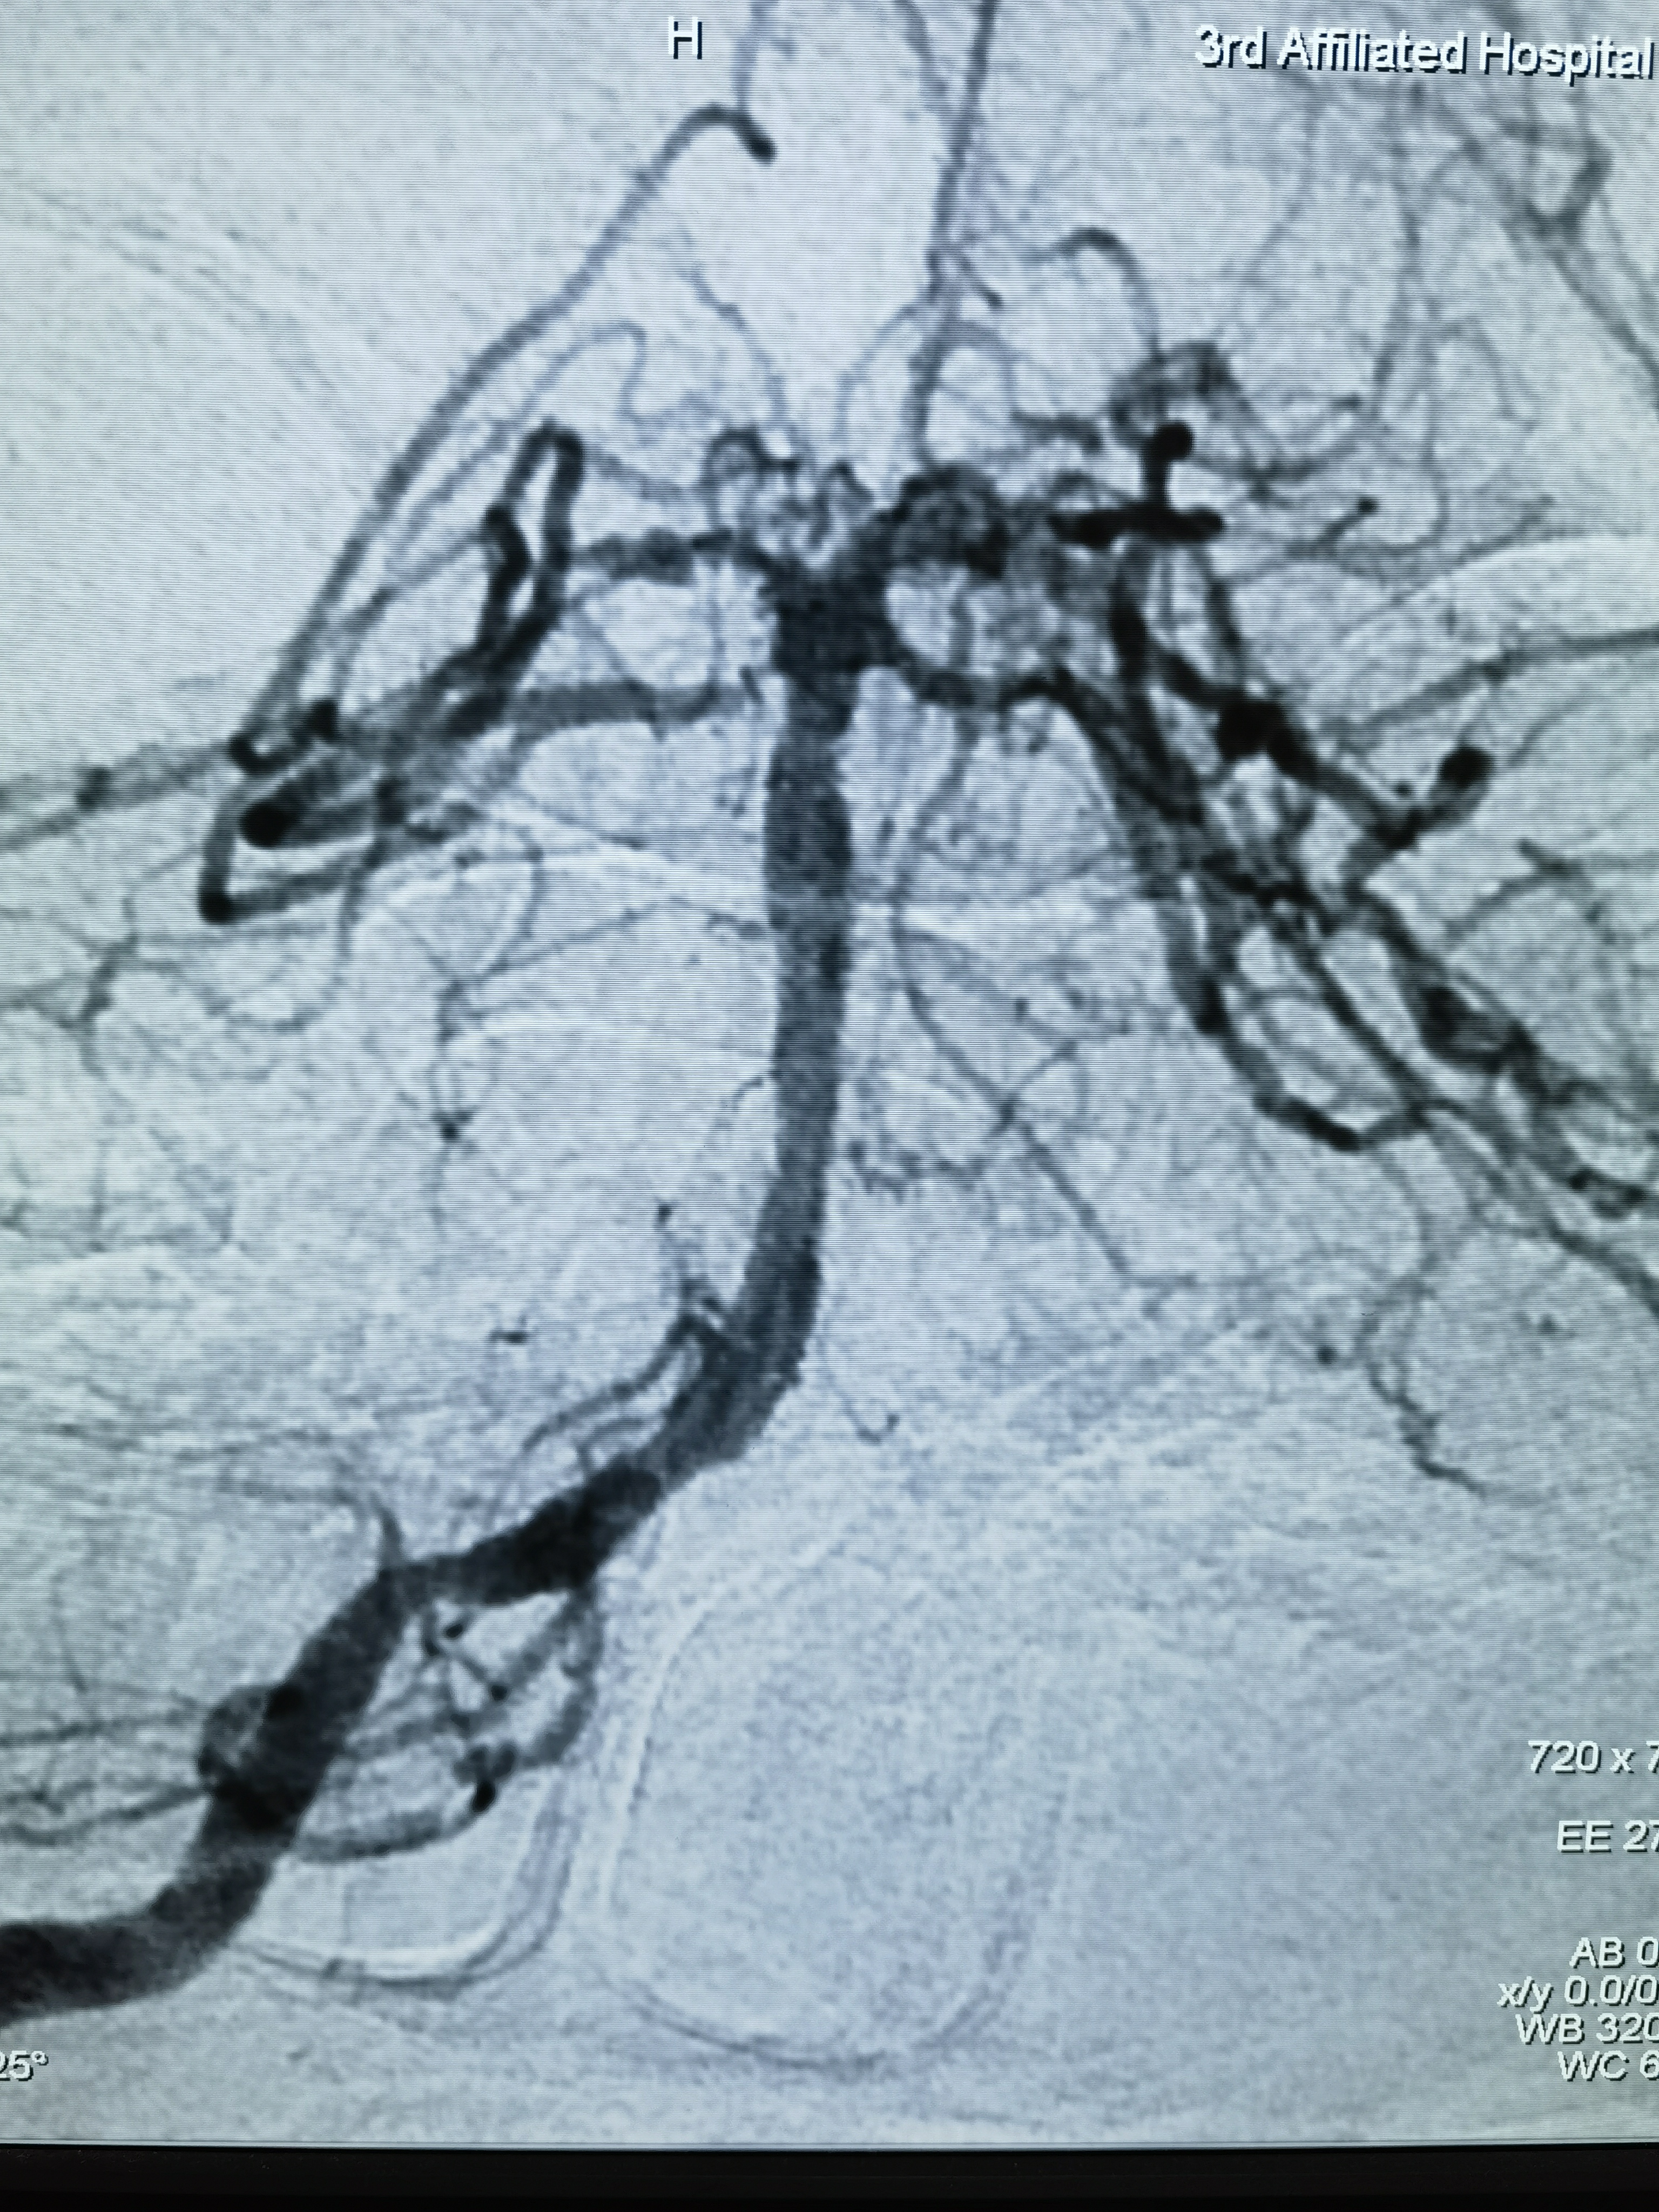

术后正位造影

释放支架后造影

蒙片看支架打开贴壁良好